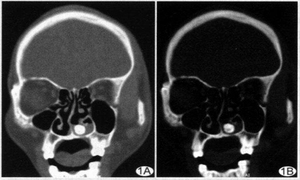

检查

需在X线观察下手术取出。